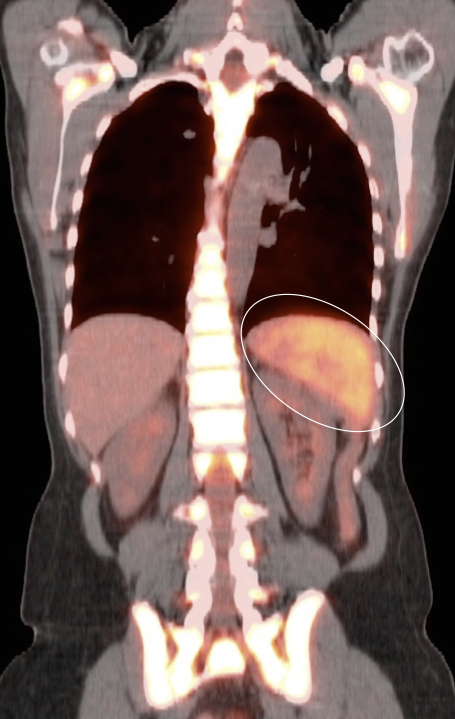

Associated splenomegaly is not uncommon.

• The uptake must be diffuse and not accompanied by lesions on the CT images.

• If uptake is focal, or if the uptake is accompanied by identifiable lesions on the co-registered CT images, malignancy must be strongly suspected.